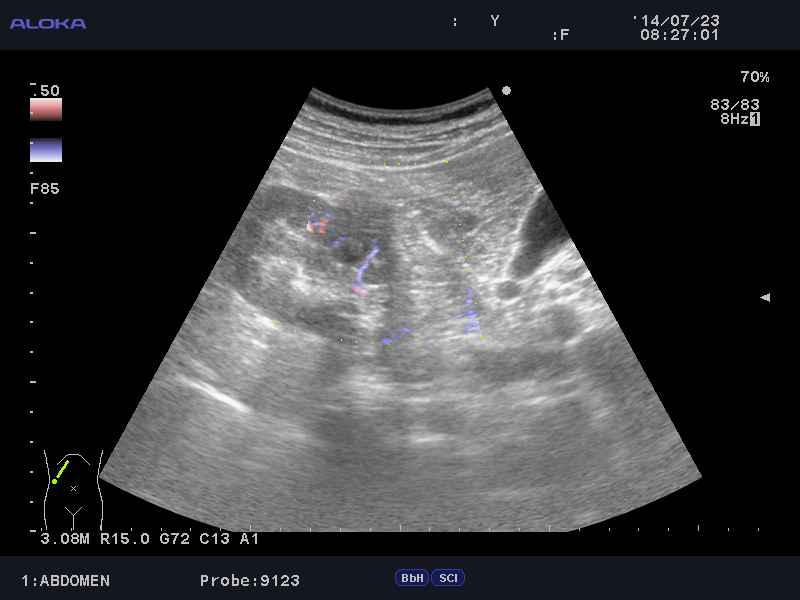

Образование в правой почке

Мужчина средних лет.Жалоб не предъявляет.

С его слов, 10 лет назад в правой почке находили кисту.

Сканер Sonoscape S40

Aloka alpha 6

Ваше мнение?

гипоэхогенное образование в среднем сегменте, деформирующее контур почки...наверное рак

Кровотока ни грамма- Киста

Динамики нет, на последнем видео четко видна киста при включенной 2й гармонике